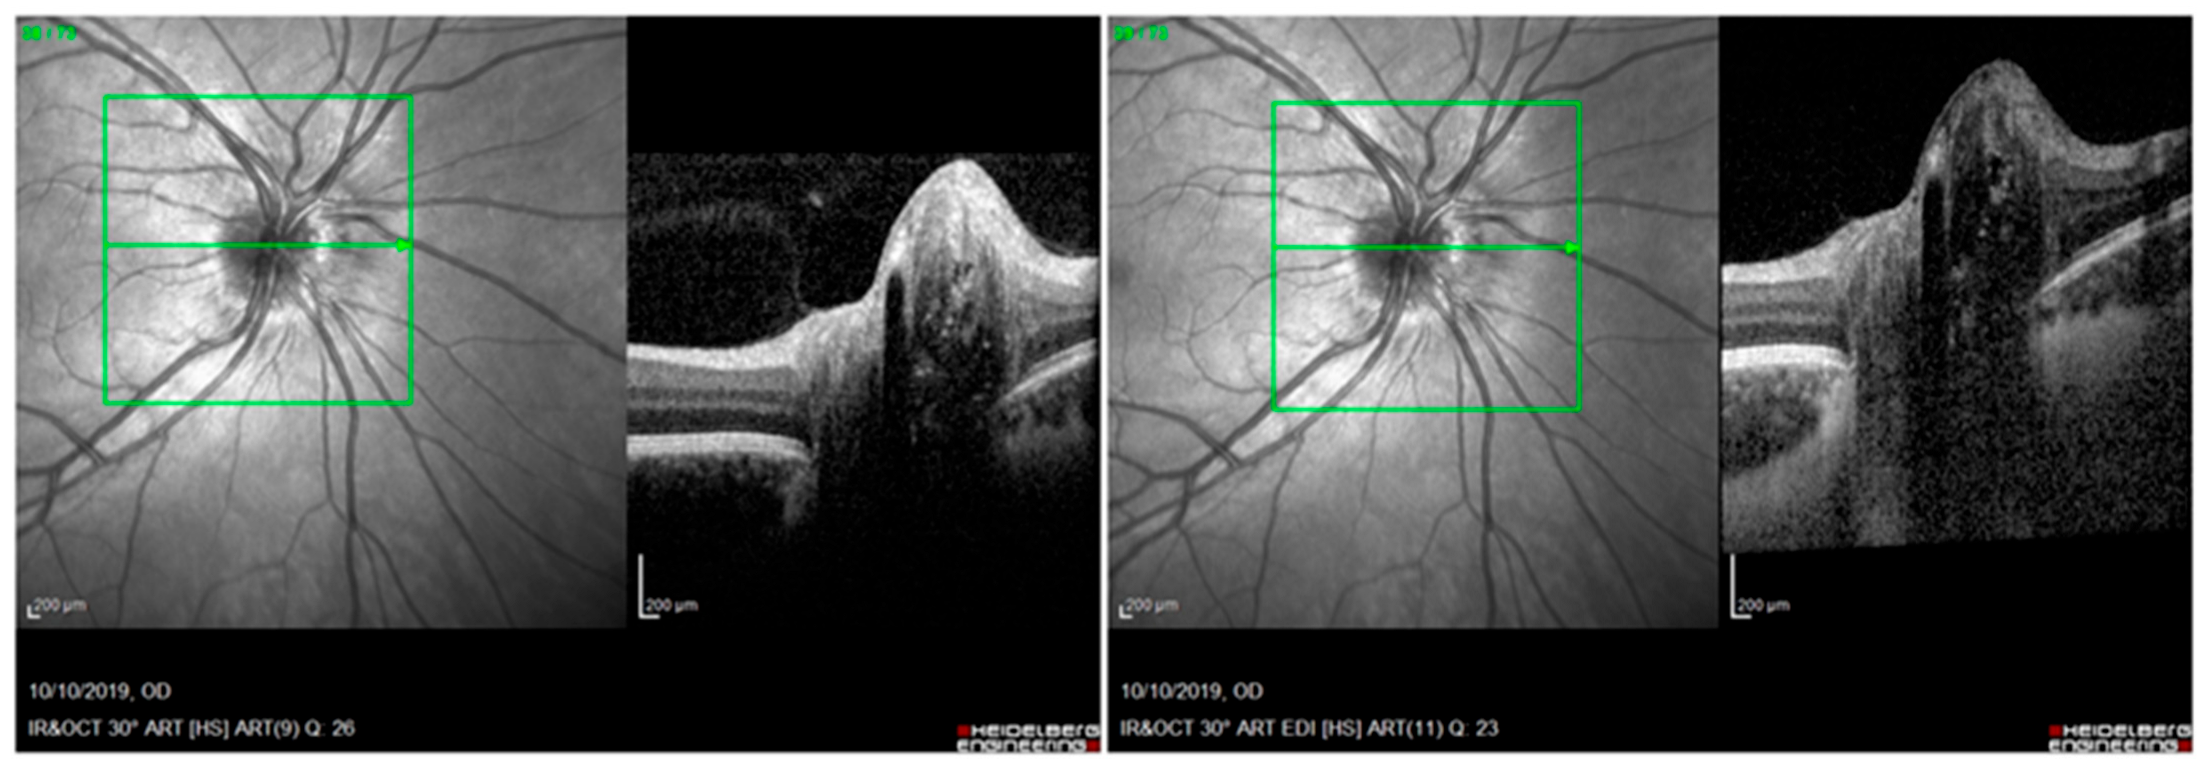

- We apologize for the misunderstanding. Figures 3 and 4 do not represent enhanced depth imaging (EDI) OCT acquisition of optic disc drusen (ODD) and peripapillary hyperreflective ovoid mass-like structures (PHOMSs). The purpose of those images was only to represent how they appear in OCT scans, and they were not used for testing OCT sensitivity to detect ODDs and PHOMSs. In our study we acquired both EDI and non-EDI images to recognize both ODDs and PHOMSs, as shown in Figure 1 and Figure 2, but only EDI images were analyzed according to ODDs consortium protocols [3]. Following the example of other similar studies [4], we decided to publish non-EDI figures, but we forgot to highlight that the selected images were not in EDI. However, to avoid misunderstandings, a detailed description of the acquiring protocols of OCT images could be useful.